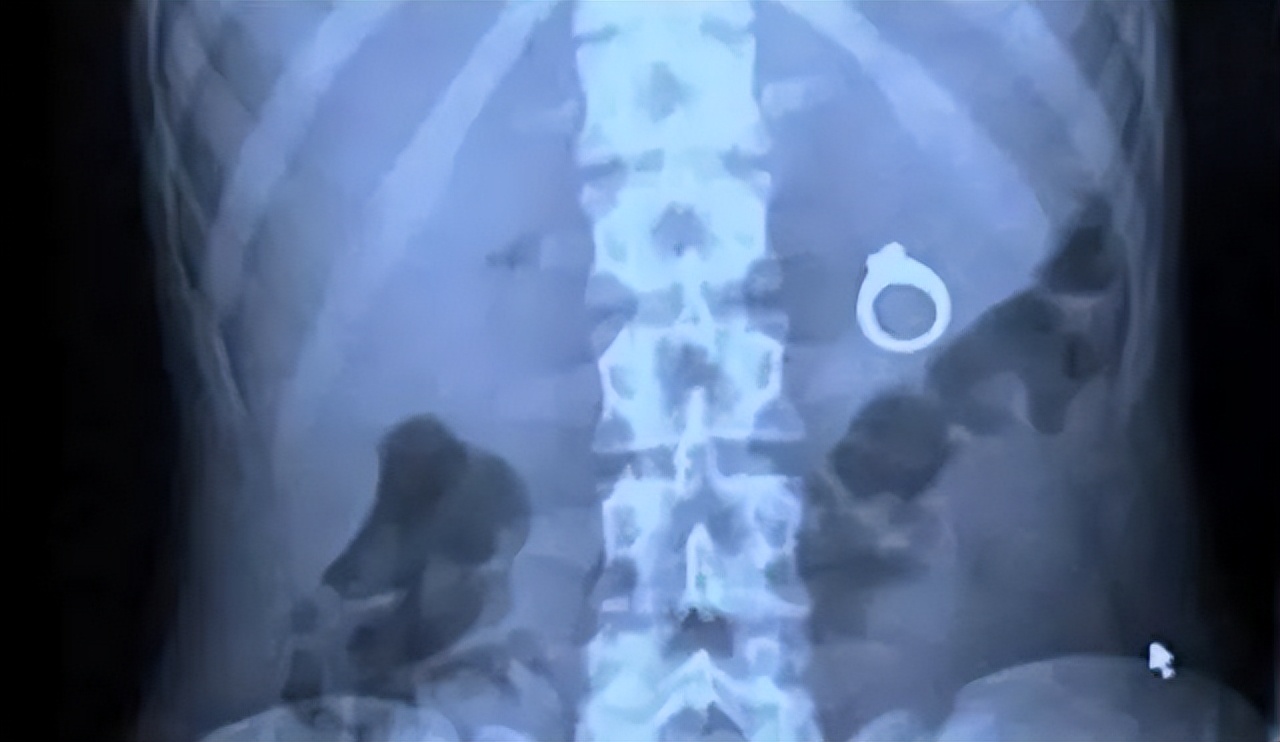

(据说是恐怖分子想吞*榴弹手**同归于尽,结果吞下去后发现无法拉环引爆)

(这告诉我们,把戒指放进蛋糕里求婚有危险)